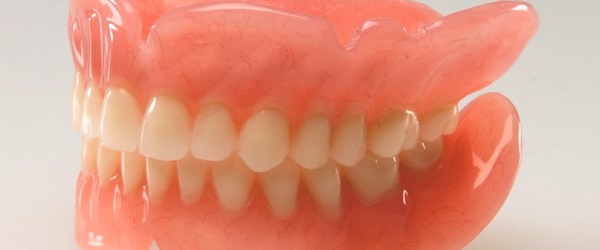

Prosthodontics (Missing Teeth)